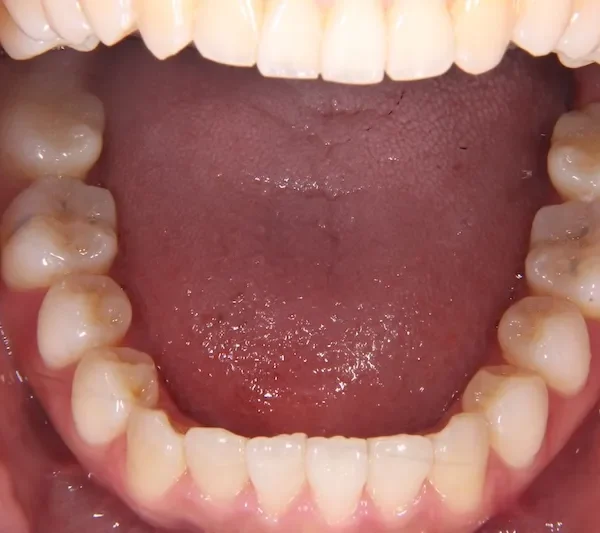

初診時

前歯で物が噛みちぎれないを主訴に来院された患者様です。

非抜歯で、オリジナルリンガルアーチと歯科矯正用アンカースクリューを用いて治療しました。

治療回数15回、1年の治療期間で矯正治療を終了しました。

主訴が改善され、ご満足頂きました。